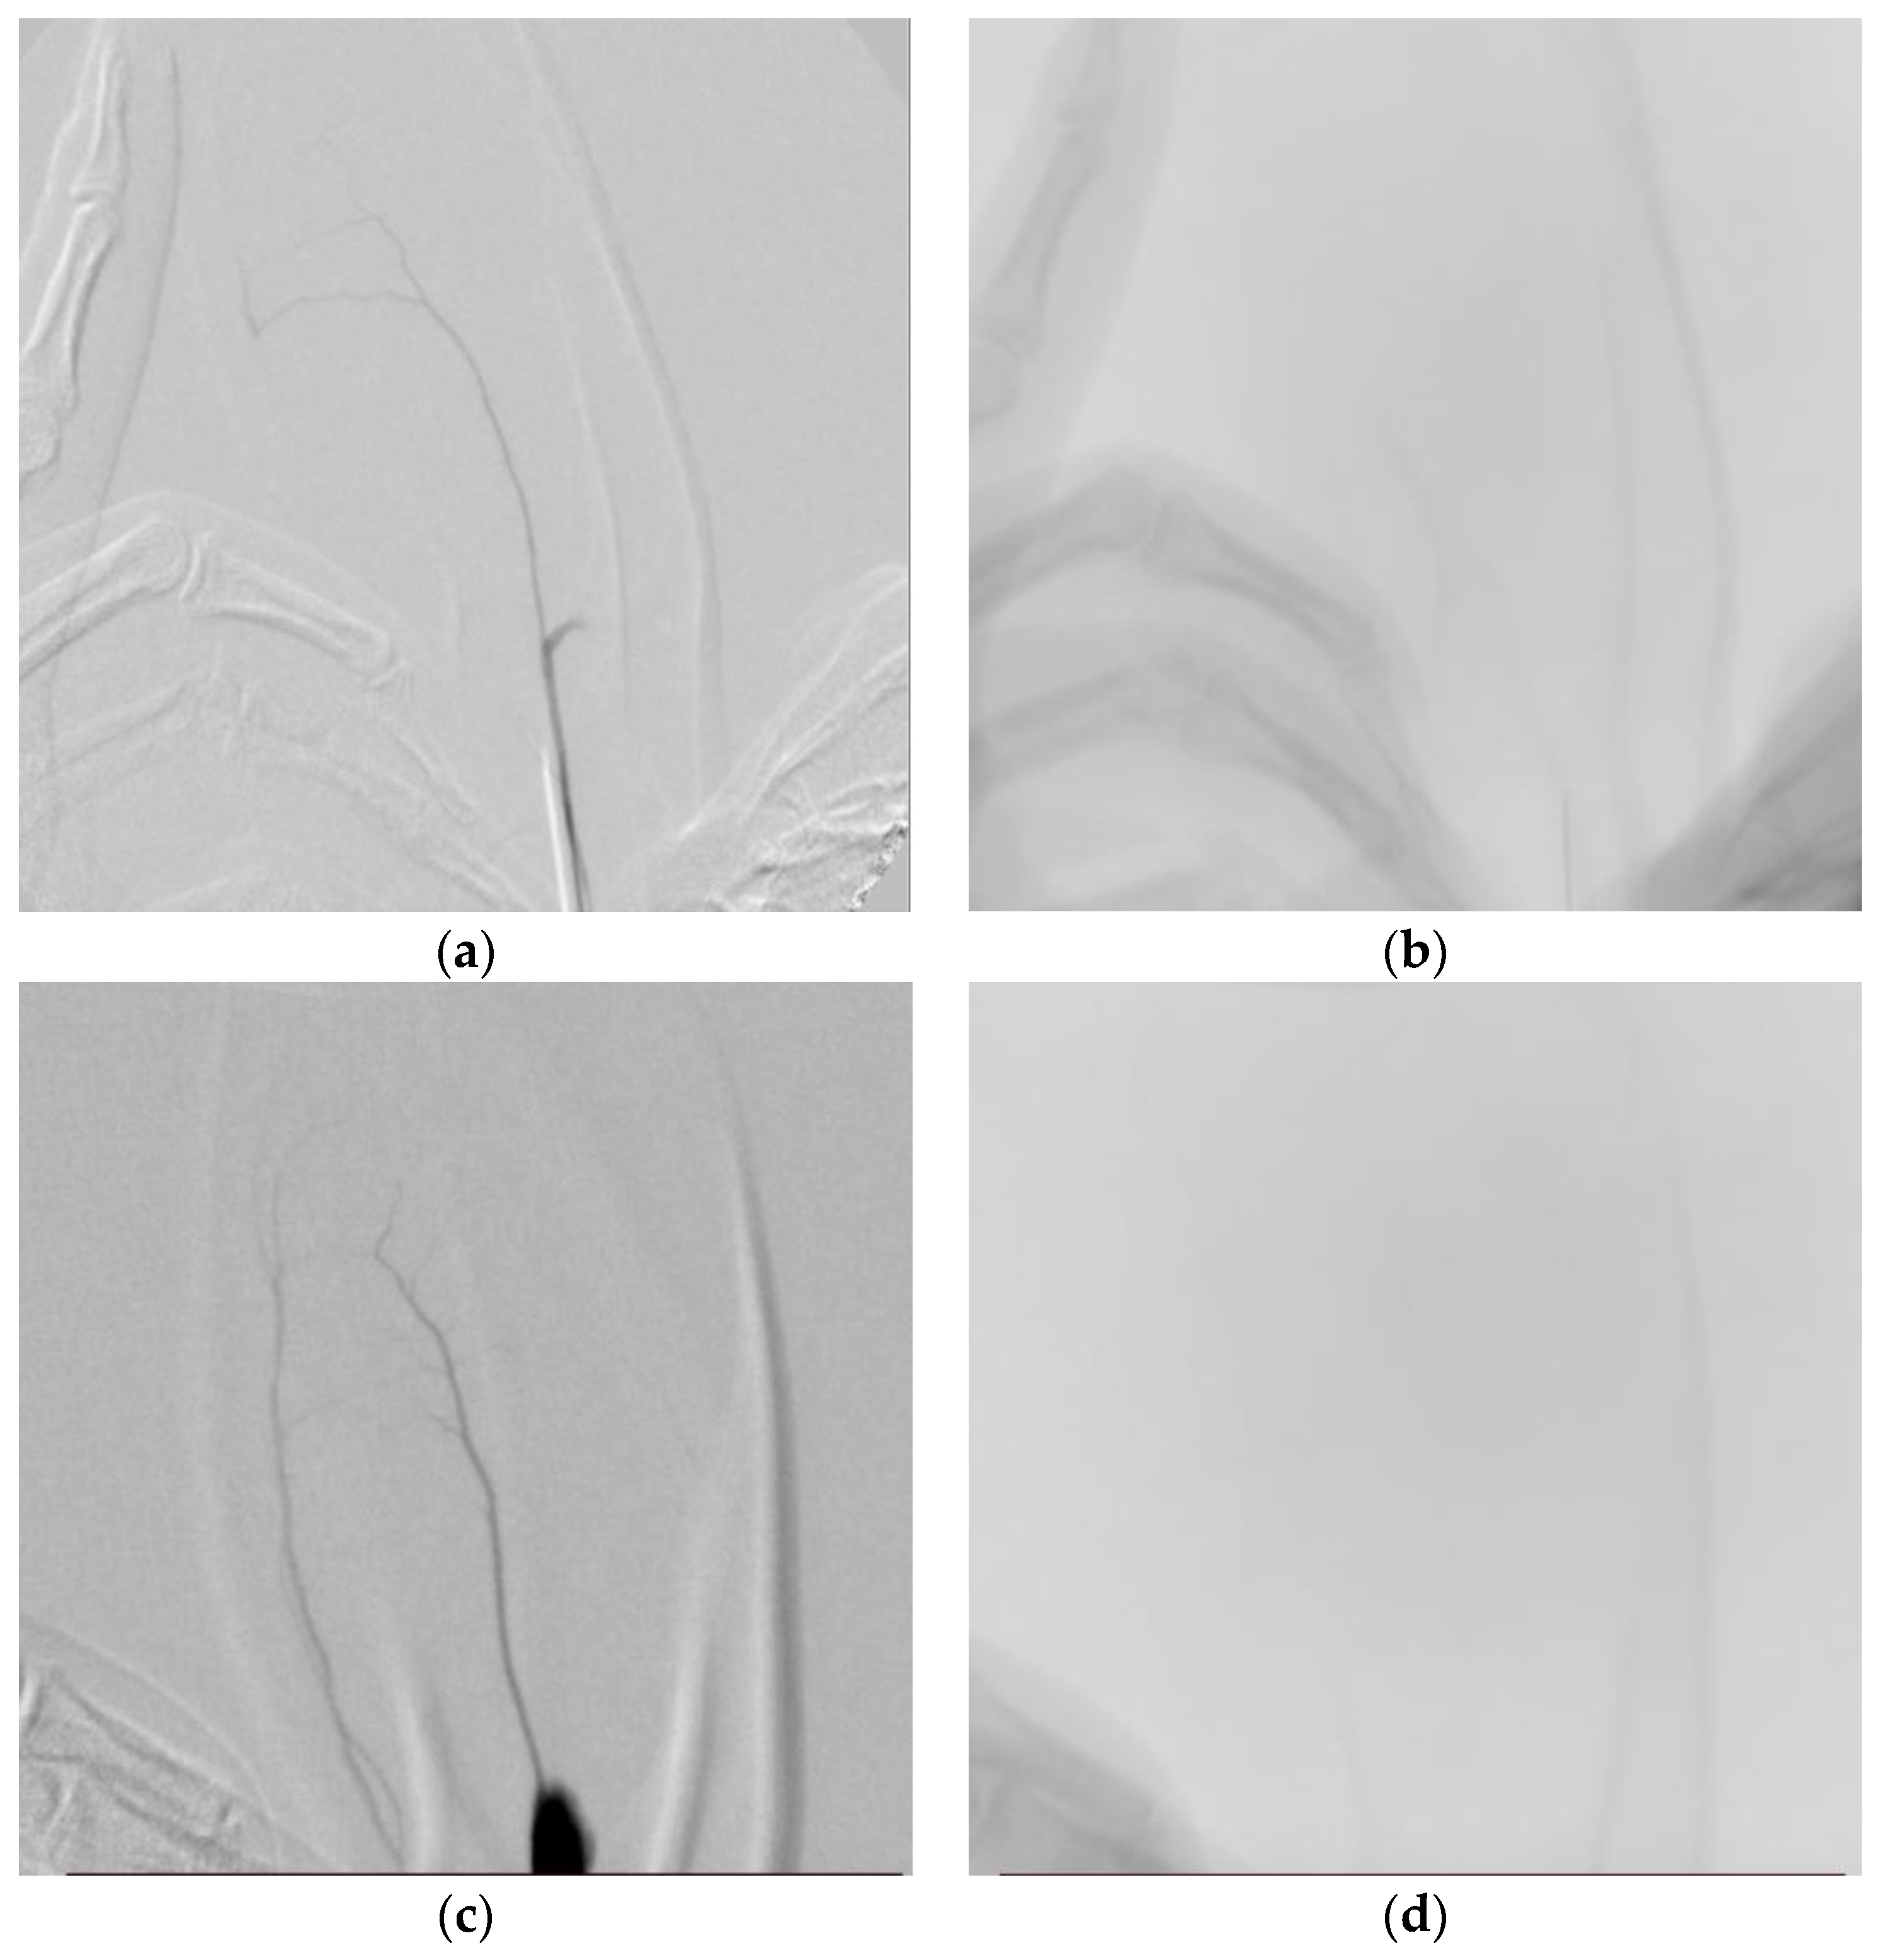

3.3. Angiographic Results